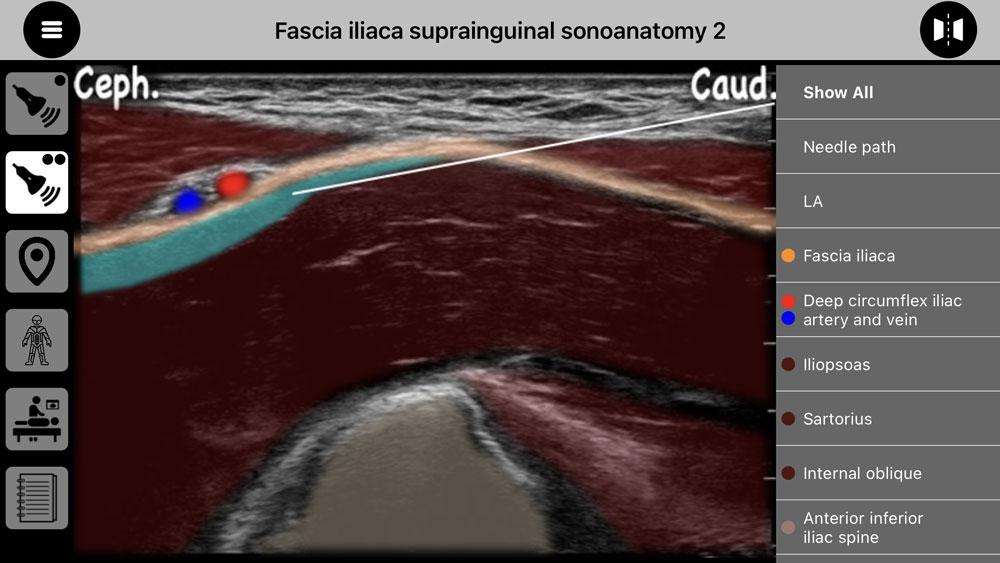

AnSo 是一种方便的资源,旨在帮助麻醉师在繁忙的手术室内以高效的方式识别常见的声解剖学。它是由对超声和局部麻醉教学感兴趣的执业麻醉师创建的。

AnSo 不仅有助于识别目标结构,还有助于识别所有周围的声解剖学。对声解剖学更全面的了解有助于检测解剖变异性,提高手术的安全性和有效性,并促进学习和教学。

AnSo 还:

- 提供声解剖学的多个示例由于每个人都是不同的,

- 提供标志性草图,有助于开发标志性结构的模式识别,并供学员在考试中绘制,

- 显示皮肤、运动、骨骼和现在可以使用多种神经块和筋膜平面块的内脏神经支配,促进适当的块选择和对预期结果的了解,

-允许组合和比较块神经支配,

-允许图像翻转以显示 L 和 R 侧方向,

- 演示功能人体工程学与患者、超声屏幕和程序主义定位对于高效的实际性能至关重要,

- 提供带有声解剖提示的块注释和实用技巧来自经验丰富的临床医生的指导,这对学习者来说非常宝贵。

- 超过 250 个超声图像,具有超过 1500 个声解剖学颜色叠加,

AnSo 是一种方便的资源,旨在帮助麻醉师在繁忙的手术室内以高效的方式识别常见的声解剖学。它是由对超声和局部麻醉教学感兴趣的执业麻醉师创建的。

AnSo 不仅有助于识别目标结构,还有助于识别所有周围的声解剖学。对声解剖学更全面的了解有助于检测解剖变异性,提高手术的安全性和有效性,并促进学习和教学。

AnSo 还:

- 提供声解剖学的多个示例由于每个人都是不同的,

- 提供标志性草图,有助于开发标志性结构的模式识别,并供学员在考试中绘制,

- 显示皮肤、运动、骨骼和现在可以使用多种神经块和筋膜平面块的内脏神经支配,促进适当的块选择和对预期结果的了解,

-允许组合和比较块神经支配,

-允许图像翻转以显示 L 和 R 侧方向,

- 演示功能人体工程学与患者、超声屏幕和程序主义定位对于高效的实际性能至关重要,

- 提供带有声解剖提示的块注释和实用技巧来自经验丰富的临床医生的指导,这对学习者来说非常宝贵。

- 超过 250 个超声图像,具有超过 1500 个声解剖学颜色叠加,